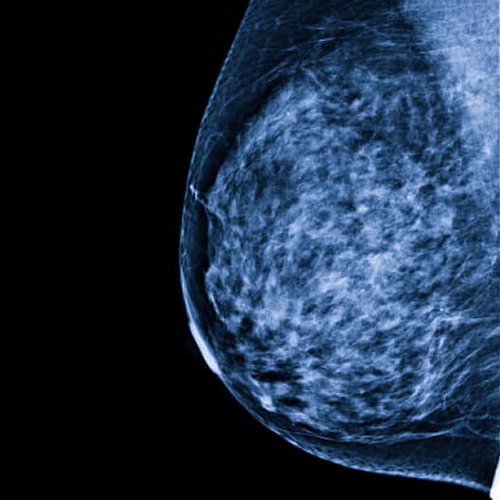

We have a huge number of cases with different modalities and regions

By Modality

By Region